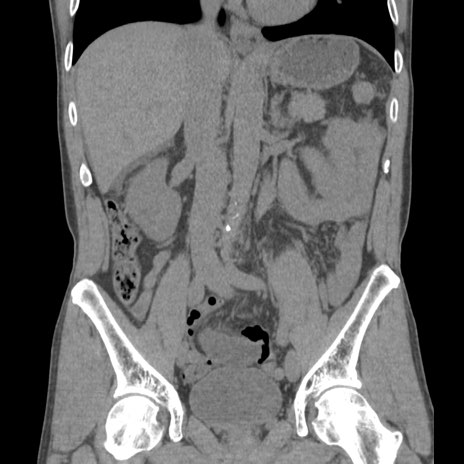

症例56 CT(冠状断像)

横断像